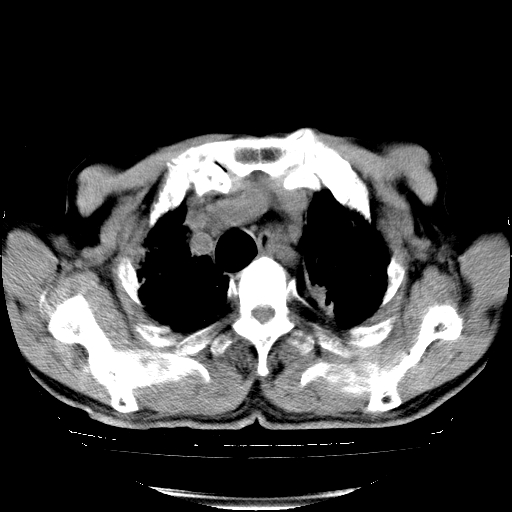

标题: CT25149:男,69岁,反复咳嗽、咳痰五年余,呼吸困难三天。 [打印本页]

男,69岁,反复咳嗽、咳痰五年余,呼吸困难三天。

慢支伴感染、肺气肿、肺心病

慢支伴感染、肺气肿、肺心病。双肺间质性改变(间质纤维化)。